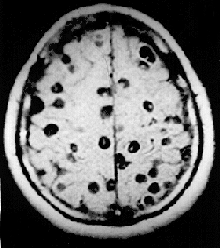

Imagem de ressonância magnética do cérebro de um paciente afectado por neurocisticercose mostrando múltiplos cisticércios no interior dó tecido cerebral.

Os Cestoda (ténia e similares) e os Digenea (tremátodes e similares) são a causa importantes patologias em humanos e em animais domésticos. Os Monogenea, parasitas de peixes, podem causar importantes perdas em instalações de aquacultura.[39] Um doença com esta origem, a bilharziose, também conhecida por esquistossomose ou doença-do-caramujo, é a segunda patologia mais expandida e devastadora da saúde das populações humanas das regiões tropicais, apenas ultrapassada pela malária.

No ano 2000, estimava-se que 45 milhões de de pessoas estavam infestadas coma ténia Taenia saginata, originária de carne bovina infestada, e 3 milhões com a espécie Taenia solium, de origem suína.[39] A infecção do sistema digestivo por ténias adultas causa sintomas abdominais considerados desagradáveis e debilitantes, mas em geral não causam incapacidade ou ameaçam a vida.[40][41] A neurocisticercose, resultante da penetração de larvas de T. solium no sistema nervoso central, é a principal causa de epilepsia adquirida a nível global.[42] Em 2000, cerca de 39 milhões de pessoas estavam infectadas com tremátodes que na natureza parasitam peixes e crustáceos, mas que podem ser transmitidos aos humanos pela ingestão da peixe ou de crustáceos crus ou mal passados. A infecção de humanos pela espécie Diphyllobothrium latum, um parasita de peixes, causa difilobotríase da qual ocasionalmente resulta deficiência de vitamina B12 e, em casos severos, anemia megaloblástica.[39]